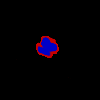

CCs exhibit lower underflow and overflow error.

We find that, compared to the baseline, CCs demonstrate more representative capacity, as evidenced by statistically significantly lower underflow and overflow across both datasets (Table 3). This representative capacity is clearly visualized in Figure 4. We also found that, for LIDC and FoggyBlob respectively, 42.96% and 50.16% of instances had (a trivial level of error) and 40.20% and 45.45% of instances had . In addition to these observations, we found that for individual instances experience less overflow than underflow () to a statistically significant degree ( for LIDC, for FoggyBlob) for LIDC and FoggyBlob respectively.

These results suggest that represents bounds on the range of singular annotations; that is, we would expect a singular annotation drawn by some annotator to fall within . Overall, the results suggest that a single CC annotation represents many uncertainty-relating structural properties across multiple singular annotations.